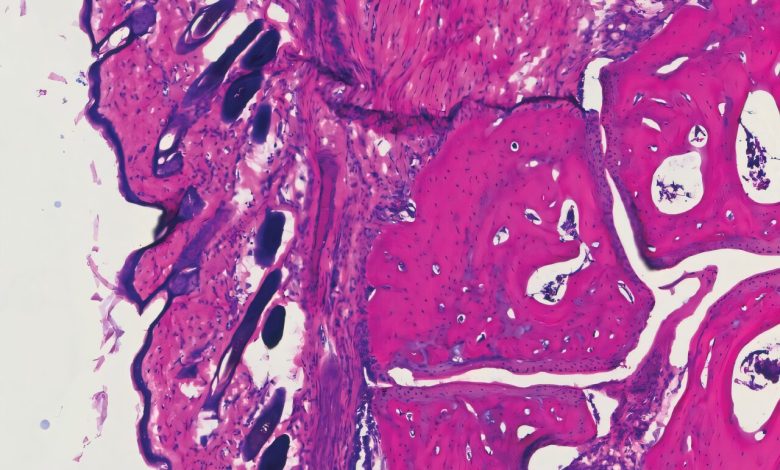

Histologia mostrando a articulação do tornozelo de um camundongo quatro dias após receber o novo tratamento com anticorpos, V11 sFc. Crédito: laboratório Ravetch,. Universidade Rockefeller

Em seguida, eles projetaram uma IgG expressa de forma recombinante para aumentar a ligação a esses receptores e os infundiram em camundongos com receptores Fc humanos nos quais haviam induzido artrite (o que significa que foram injetados com soro isolado de um camundongo com artrite natural). Um grupo semelhante de camundongos artríticos foi tratado com a infusão convencional de IVIG.

Ambos os grupos se beneficiaram da infusão, observando redução do inchaço nas articulações. Mas as doses eram dramaticamente diferentes: foram necessárias 100 vezes mais IVIG para alcançar o mesmo efeito que uma dose da nova molécula.